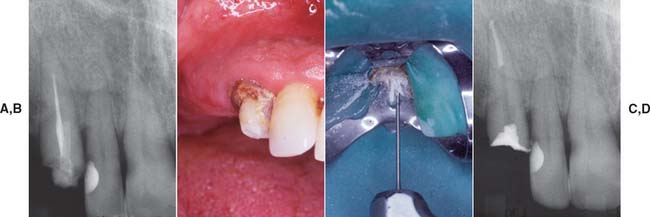

Because of extensive caries or periodontal disease, removal of a tooth may be more sensible than endodontically treating it, although a severely damaged tooth occasionally can be restored after orthodontic repositioning or root resection (Fig. 12-1; see also Fig. 16-7). This should be done if loss of the tooth will significantly jeopardize the patient’s occlusal function or the total treatment plan, particularly if dental implants are not an option. When the decision is made to treat the tooth endodontically, consideration must have been given to its subsequent restoration. Before being restored, teeth that have been endodontically treated must be carefully evaluated for the following1:

Fig. 12-1 A to D, A severely damaged tooth can sometimes be retained after orthodontic extrusion (see Chapter 6). E and F, Plaque control around periodontally compromised teeth may be improved after hemisectioning (see Chapter 5).

(E and F, Courtesy of Dr. H. Kahn.)